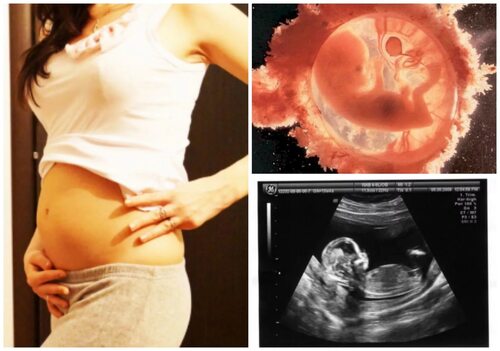

На 12-13 неделе беременности плод продолжает активно развиваться, приобретая все более человеческий вид. В этот период плод уже обладает различными чертами лица, пальцы на руках и ногах формируются, а тело начинает пропорционально увеличиваться.

Фотографии плода на 12-13 неделе беременности

В нашей подборке представлены фотографии плода на 12-13 неделе беременности, которые помогут вам представить, как выглядит малыш в это время. Замечательно, как его черты становятся более выраженными, а тело приобретает все больше сходства с новорожденным.

Учтите, что каждая беременность индивидуальна, и развитие плода может немного отличаться в зависимости от множества факторов. Фотографии представлены лишь в общем плане и не могут отобразить точное положение вашего ребенка.